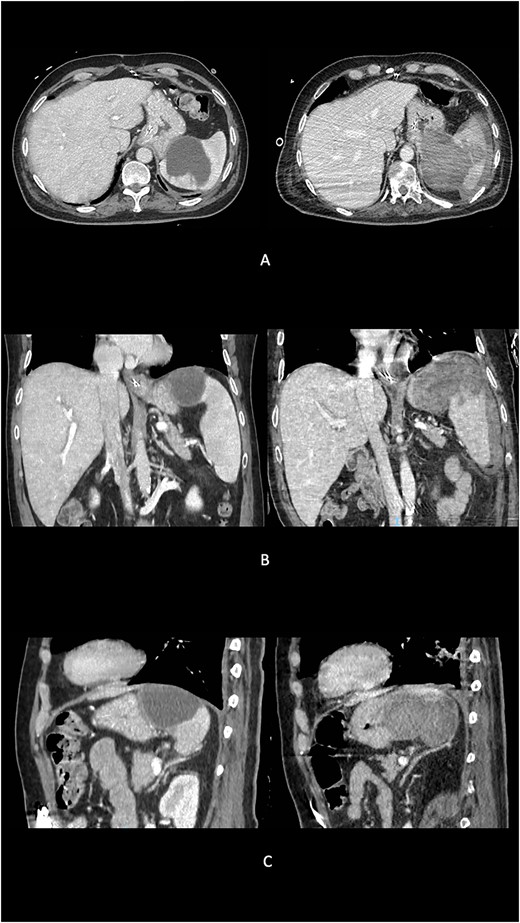

A transesophageal echocardiogram revealed hyperechoic images in both mitral valve leaflets with medium-grade valve insufficiency and tricuspid dysfunction. Peripheral venous blood cultures yielded negative results, and empiric antibiotic therapy was initiated. Infective mitral valve endocarditis was staged using an abdominal computed tomography (CT) scan with contrast medium, which identified an 8 × 7 cm neoformation at the upper pole of the spleen, consistent with an abscess lesion (Fig. 1).

Preoperative evolution of splenic abscess into GSF at imaging. (A) Axial scans. (B) Coronal scans. (C) Sagittal scans.

Three months after the diagnosis of splenic abscess, the patient experienced a sudden onset of anemia and melena. An abdominal CT scan revealed a large blood collection (maximum axial diameter of 10 cm, cranio-caudal extension of 15 cm) replacing the upper pole of the splenic parenchyma (Fig. 1). The splenic capsular profile was disrupted, and the blood collection extended medially, affecting the gastric fundus wall and entering its lumen.